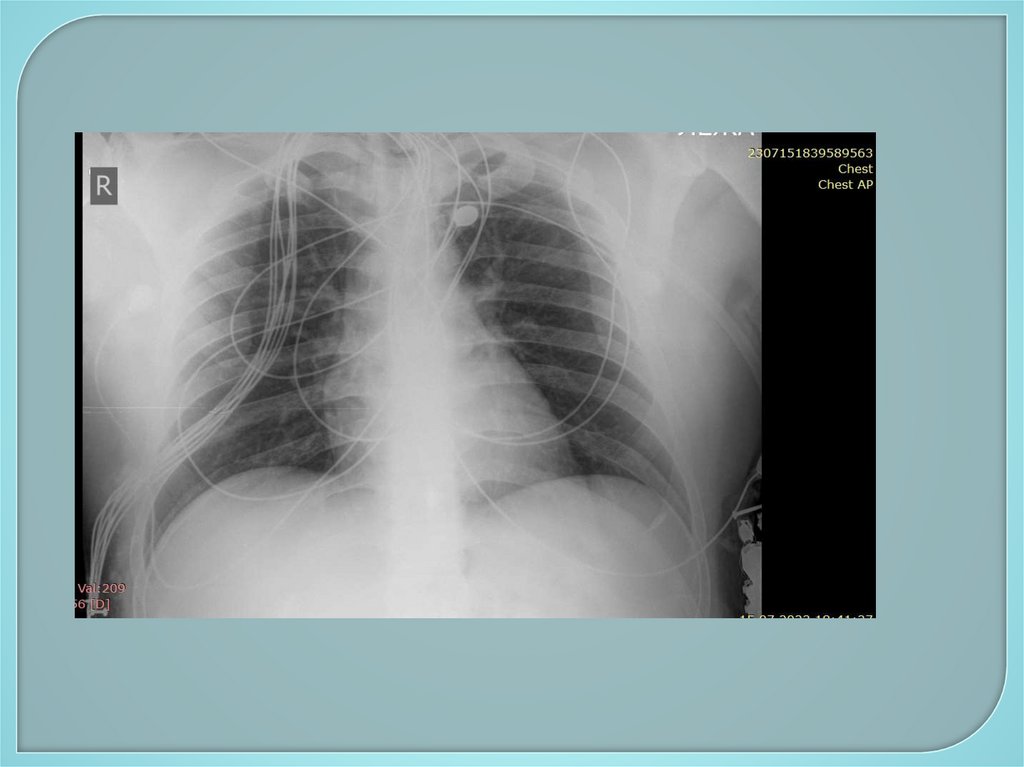

101. Дополнительное обследование

Инструментальные методы:

1. Рентгенологические методы –

рентгенография грудной клетки,

флюорография, бронхография,

компьютерная томография